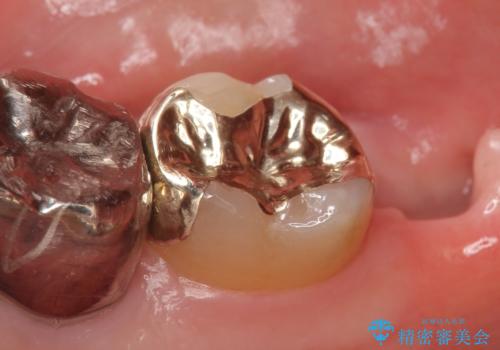

根管治療専門の医院にて処置後、被せもののの製作依頼で来院されました。土台の歯の高さがあまりに低く、しかも周りには粘膜しかない状態でした。このままではペラペラな被せものしか作れず、長期的な予後は見込めません。

歯冠長延長術と角化歯肉の移植を行い、土台の歯に十分な高さを与えると共に周囲に丈夫な歯ぐきを整え、より長期にわたって使っていけるブリッジを製作することができました。

被せものの種類:高透過フルジルコニア ベレッツァ